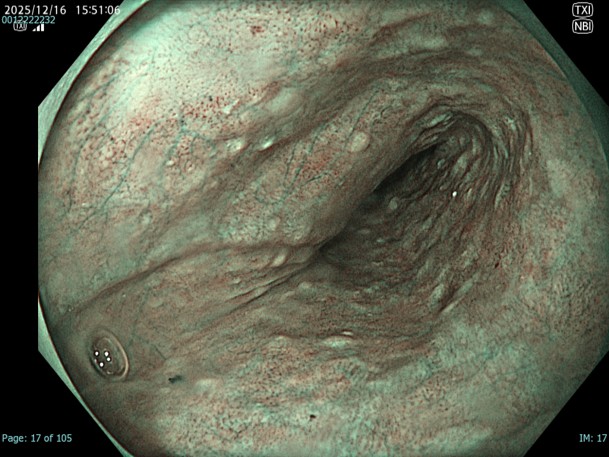

• 白色光観察(中遠景)

強調設定:A3

図1

胸部中部食道でやや粗造で血管透見が落ちているが、明かなDLは指摘が困難であり、色調も周囲粘膜とほぼ同等の為、この画像のみで腫瘍性変化を診断することは困難である。